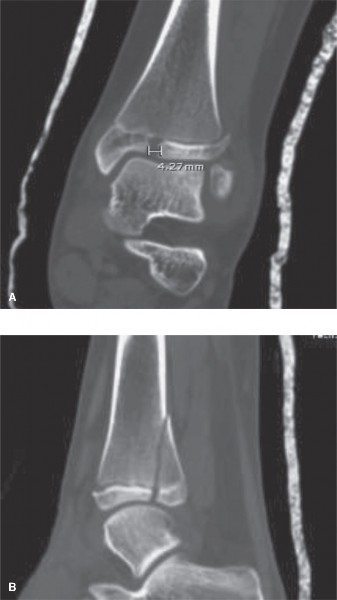

The initial anteroposterior (AP) and lateral radiographs of the right femur demonstrate a complete, displaced, length-stable transverse fracture of the middle third of the femoral diaphysis. There is minimal comminution. The traction splint has effectively restored length, though there remains slight apex-lateral and apex-anterior angulation.

Crucially, dedicated AP and lateral views of the right hip and right knee are obtained. The femoral neck is intact, with no evidence of a basicervical or transcervical fracture—a classic "missed injury" in the setting of high-energy femoral shaft fractures. The distal femoral physis is open and symmetric, with no widening or displacement to suggest a concurrent Salter-Harris injury.

Instead, the diagnostic focus shifts to meticulous radiographic templating. The narrowest portion of the medullary canal (the isthmus) is measured on both the AP and lateral projections. The fundamental rule for Elastic Stable Intramedullary Nailing (ESIN) dictates that the combined diameter of the two selected nails should fill approximately 80% of the narrowest diameter of the medullary canal. Therefore, the formula used is:

(Narrowest Canal Diameter in mm) × 0.4 = Optimal Single Nail Diameter.

In this patient, the isthmus measures 10 mm. Thus, two 4.0 mm titanium elastic nails will be selected to provide optimal biomechanical stability.